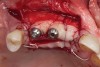

Fig 9. The implants and healing caps were placed.

Figure 9